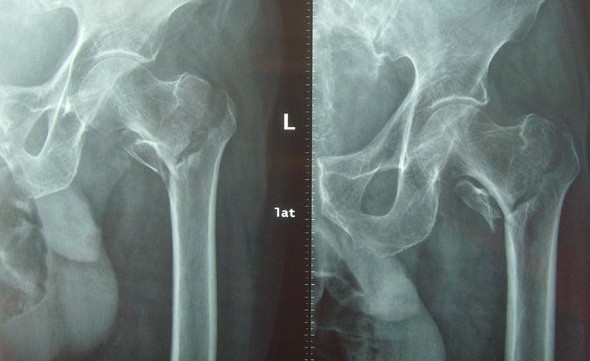

股骨粗隆间骨折

由于粗隆间局部以松质骨为主,高龄老人均有明显的骨质疏松,伤后容易发生不稳定的粉碎性骨折。同时,高龄老年患者,伤前常伴有各种内科疾病,无论采取何种治疗方式,对老年患者都具有风险。

保守骨牵引和内固定手术后都不能达到早期下床活动的目的,其负重下床活动均以骨折良好骨性愈合为前提,而长期卧床极易发生坠积性肺炎、压疮、泌尿系感染、深静脉血栓等严重并发症。采用人工关节置换术是此类骨折的一种积极有效、最直接的治疗手段,能提供早期的关节活动,一般情况下,患者术后下地时间在1周以内(内固定患者多需4~6周),减少了卧床时间,降低因长期卧床导致并发症的发生率。

人工股骨头置换术治疗高龄股骨粗隆间骨折,基本不涉及骨愈合, 故不须长期制动,术后髋关节功能恢复较快,是该术式最吸引骨科医生和患者的优点。